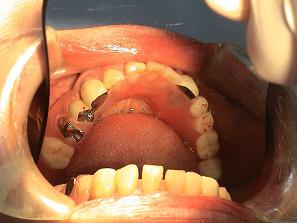

3.

バネなし入れ歯を入れた

状態です!!

* 金属のバネがないので

見栄えが良いです!

入れ歯が入っているとは

気がつかれにくいです!!